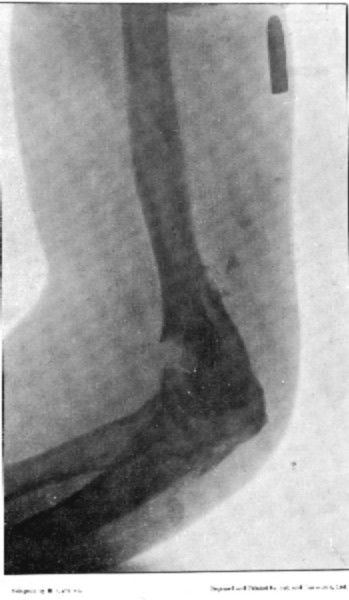

6. Comminuted Fracture of Humerus due to Oblique Impact184

7. Same Fracture healed186